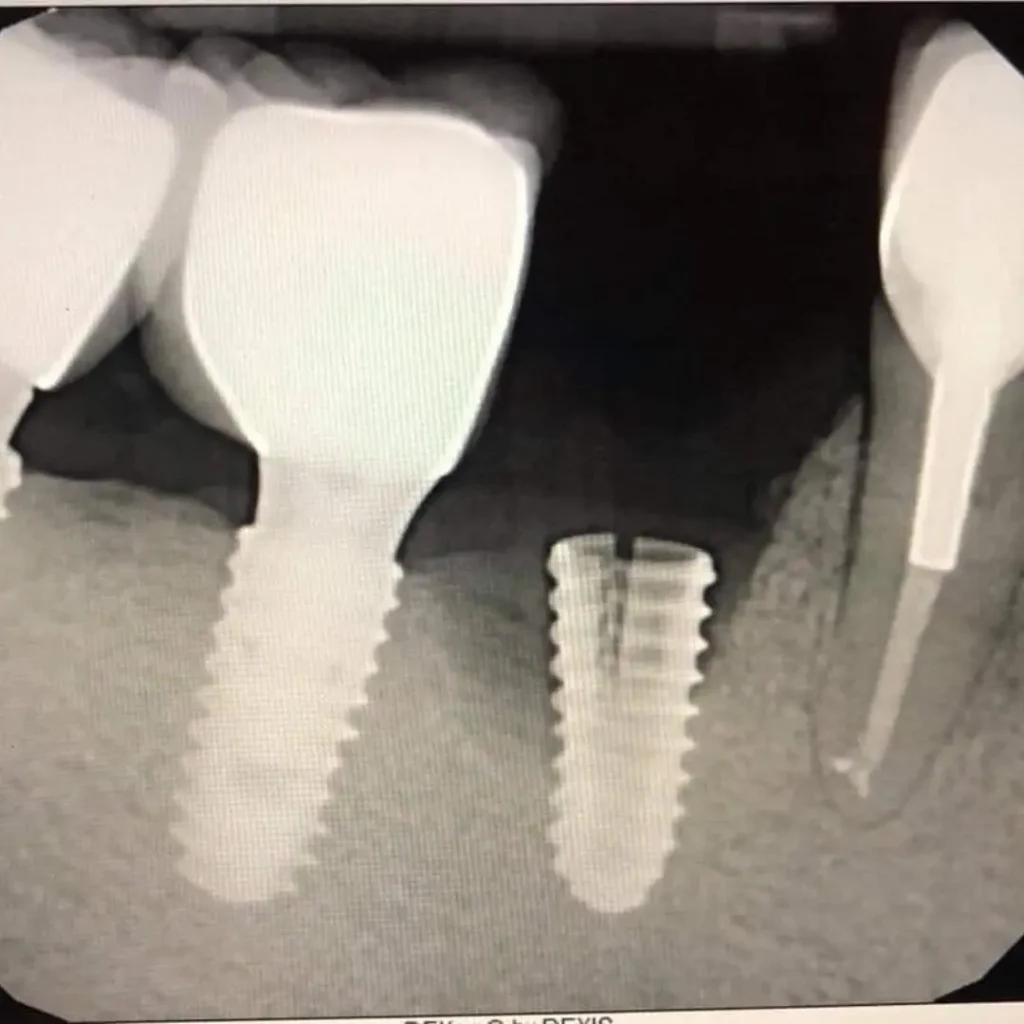

- Advanced Technology - for fast, accurate diagnostics and implant repairs

In cases where there’s bone loss, a bone graft may be required to rebuild the area before the dental implant procedure. Our specialists will evaluate your condition and develop a personalized treatment plan.